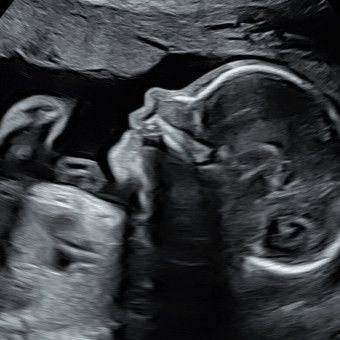

Holly Taylor & William Wood

Liberty, SC

June 15, 2026